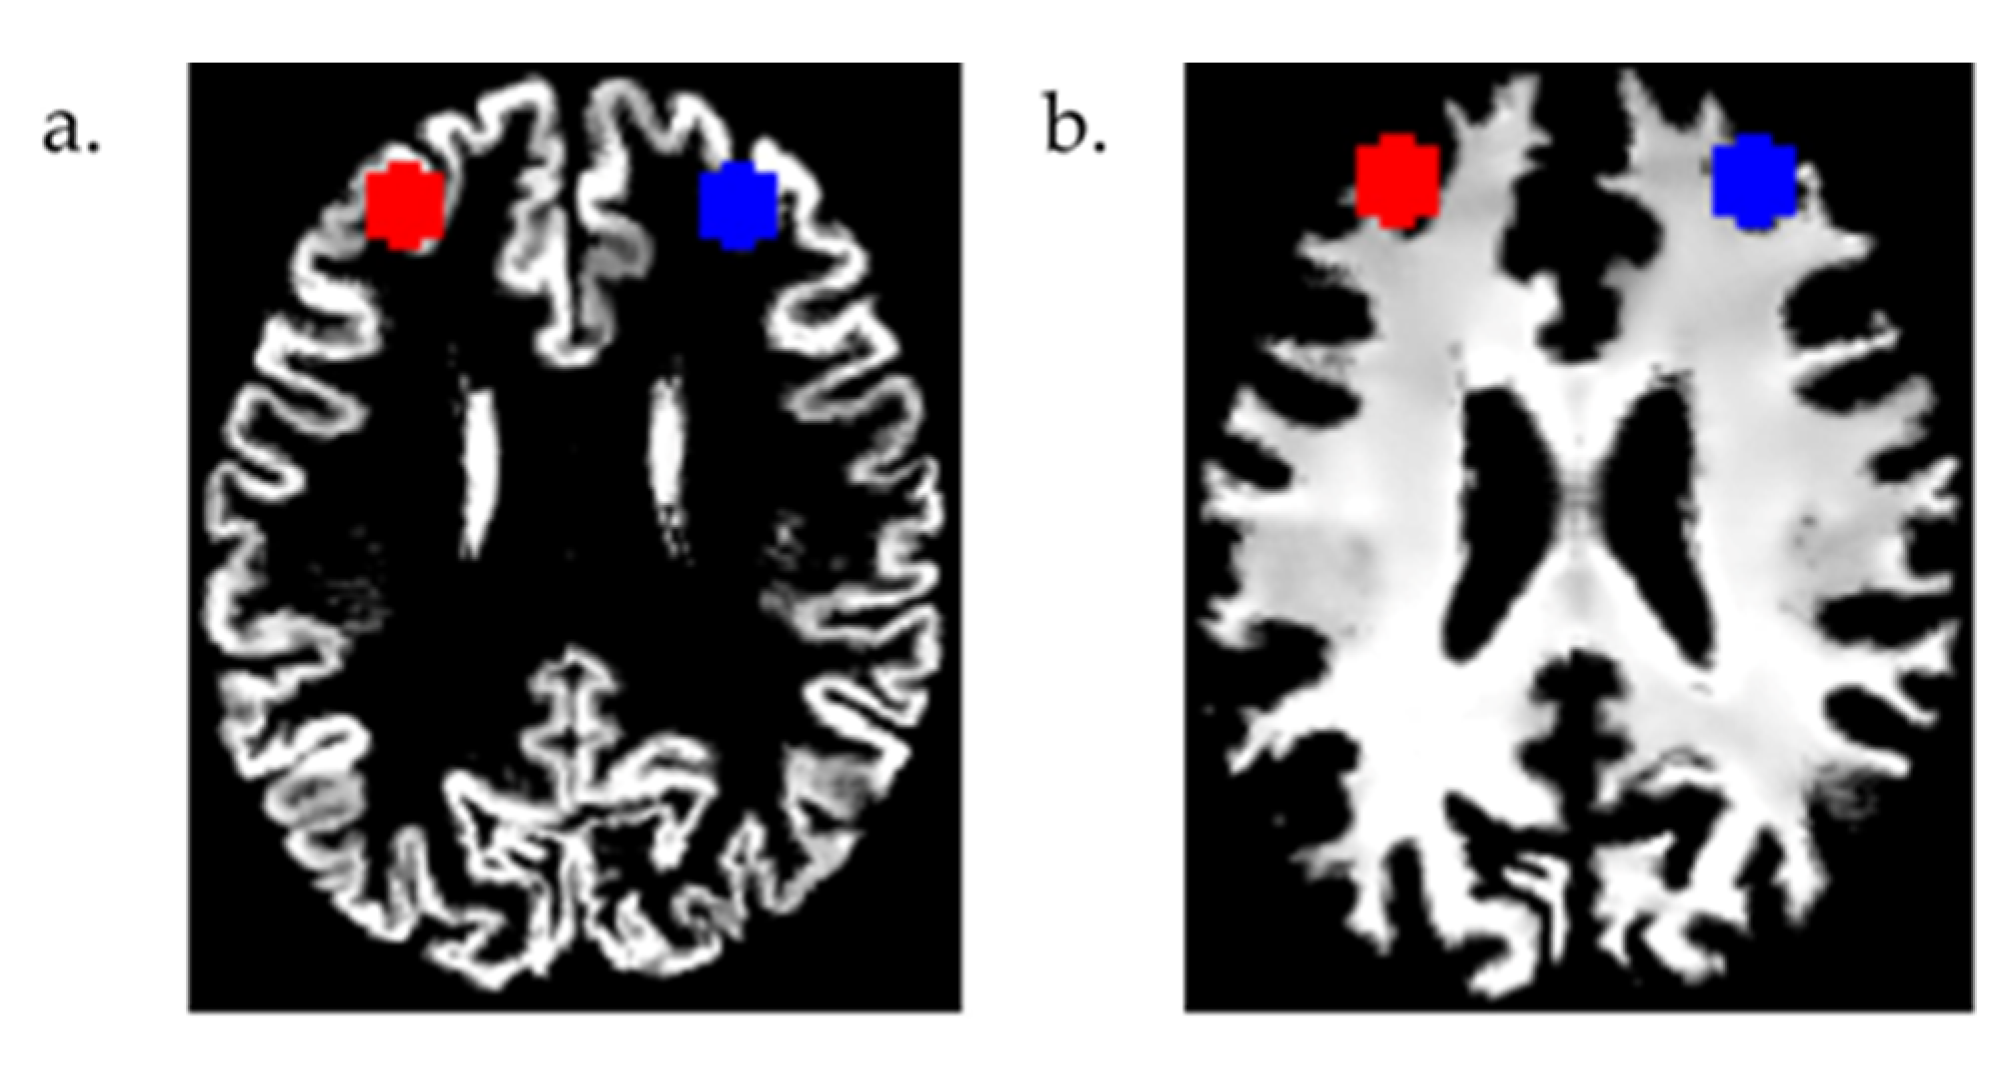

Since the participants received rTMS treatments targeting both the left and right DLPFC, we created bilateral ROI masks using two 8 mm radius spheres centered at MNI coordinates x = 30, y = 43, and z = 23 (right DLPFC), and x = −30, y = 43, and z = 23 (left DLPFC) in the MarsBar [24] toolbox (v0.45, http://marsbar.sourceforge.net/, accessed on 28 March 2022). These MNI coordinates of the DLPFC, reported in previous studies [25,26], are slightly deeper than the Talairach coordinates (x = ±50, y = 30, and z = 36), in which the coil position and direction are specified using the BrainSight 2 software (Rogue Research, Montreal, QC, Canada) in the clinical trial of rTMS [17]. Instead of using these Talairach coordinates, because of their proximity to the skull, we used the MNI coordinates of the DLPFC [25,26] mentioned above to develop the two ROI masks. These masks were resliced, and the volumes from the modulated and warped GM and WM images were then calculated using the get_totals.m script by G. Ridgeway (http://www0.cs.ucl.ac.uk/staff/g.ridgway/vbm/get_totals.m, accessed on 1 April 2022). The overlays of these masks on a participant’s modulated and warped GM and WM images are shown in Figure 1 using the MRIcron [27] software (v1.0.20190902, University of South Carolina, Columbia, SC, USA, https://people.cas.sc.edu/rorden/mricron/, accessed on 15 August 2023).

Figure 1.

The left (red) and right (blue) dorsolateral prefrontal cortex (DLPFC) masks are shown on the modulated and warped (a) gray matter and (b) white matter images (axial view) of a participant.